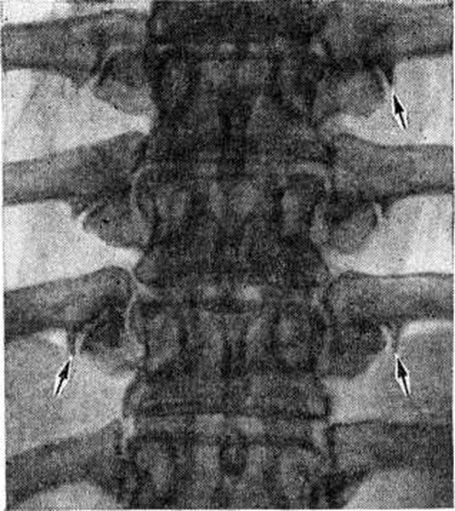

Остеоартрит фасеточных суставов: медицинские снимки и схемы